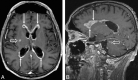

CNS lymphoma consists of 2 major subtypes: secondary CNS involvement by systemic lymphoma and PCNSL. Contrast-enhanced MR imaging is the method of choice for detecting CNS lymphoma. In leptomeningeal CNS lymphoma, representing two-thirds of secondary CNS lymphomas, imaging typically shows leptomeningeal, subependymal, dural, or cranial nerve enhancement. Single or multiple periventricular and/or superficial contrast-enhancing lesions are characteristic of parenchymal CNS lymphoma, representing one-third of secondary CNS lymphomas and almost 100% of PCNSLs. New CT and MR imaging techniques and metabolic imaging have demonstrated characteristic findings in CNS lymphoma, aiding in its differentiation from other CNS lesions. Advanced imaging techniques may, in the future, substantially improve the diagnostic accuracy of imaging, ultimately facilitating a noninvasive method of diagnosis. Furthermore, these imaging techniques may play a pivotal role in planning targeted therapies, prognostication, and monitoring treatment response.